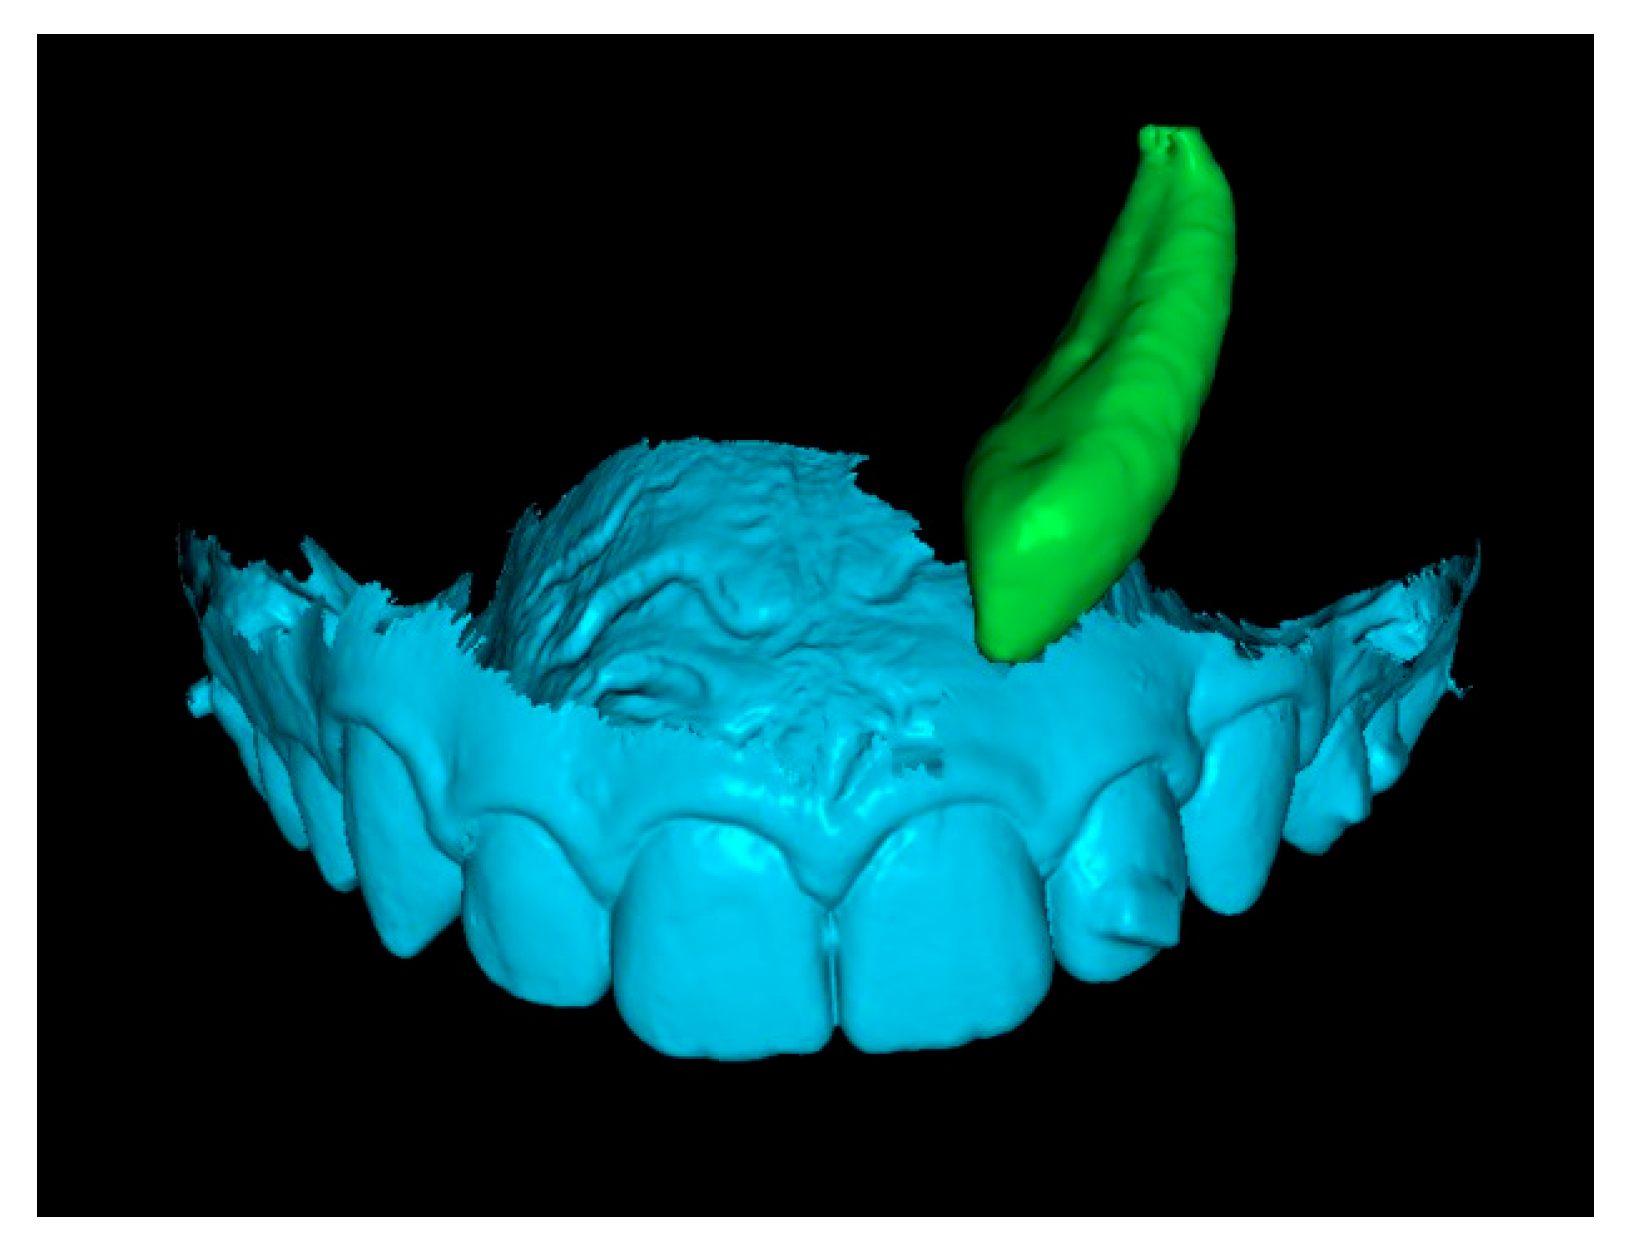

Since orthodontic traction had not yet started, the position of the teeth remained unchanged between scans, allowing precise registration. As a result, the initial STL was effectively combined with the three-dimensional position of the IC derived from the CBCT (Figure 5).

Figure 5.

Initial STL with the IC from the CBCT scan.

Third step: Overlay of Initial STL with IC and Final STL.

The initial STL combined with the IC was superimposed onto the final STL by marking stable reference points on the palatal rugae (Figure 6). This process resulted in a final STL model that includes the initial position of the IC (Figure 7).